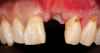

(35.) An implant being inserted into the prepared osteotomy of a patient who presented for the replacement of the maxillary left central incisor.

Figure 35